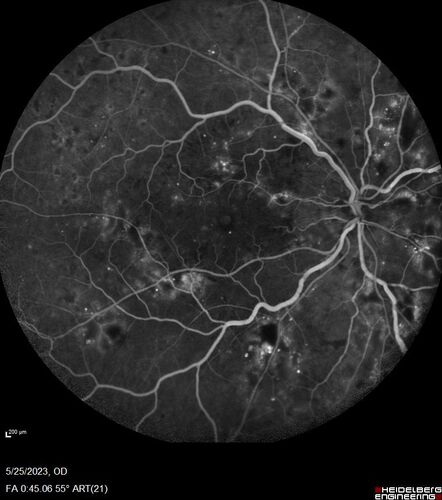

Siegrist Streaks and severe diabetic macular edema

56 year old female who presents four years after developing necrotizing fascitis and multiple organ failure from an infected foot from a roofing nail.  Her vision was 20/100 OU.  She has multiple peripheral pigment spots consistent with Siegrist streaks.